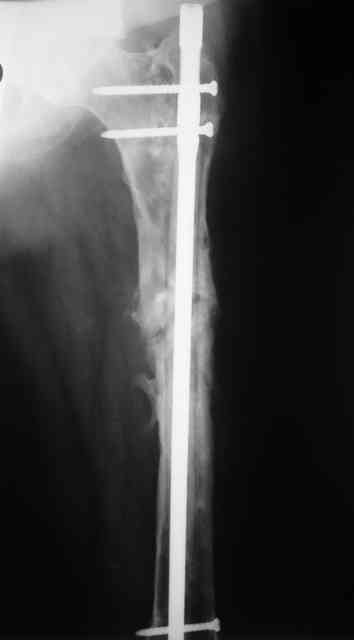

Re: Proximal femoral shaft nonunion + osteomyeliti

Вчера наш пациент был на контрольном осмотре. Вроде все идет нормально. Рентгенограммы от 25 сентября 2007 г. (прошло 5 месяцев после операции) прилагаю.